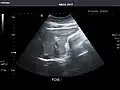

Liver: Diffusely homogeneous and normal in echogenicity. No focal mass or contour nodularity. No intrahepatic biliary ductal dilatation.

Portal Vein: Patent main portal vein.

Liver -